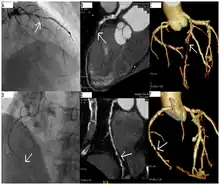

Angiography (left) and CT (middle and right) of chronic total occlusion lesions at the left anterior descending coronary artery (LAD) and right coronary artery (RCA).

CT angiography can act as a less invasive alternative to Catheter angiography. Instead of a catheter being inserted into a vein or artery, CT angiography involves only the injection of a CT-visible dye into the arm or hand via an IV line. CT angiography lowers the risk of arterial perforation and catheter site infection. It provides 3D images that can be studied on computer, and also allows measurement of heart ventricle size. Infarct area and arterial calcium can also be observed (however those require a somewhat higher radiation exposure). That said, one advantage retained by Catheter angiography is the ability of the physician to perform procedure such as balloon angioplasty or insertion of a stent to improve blood flow to the artery.[8]